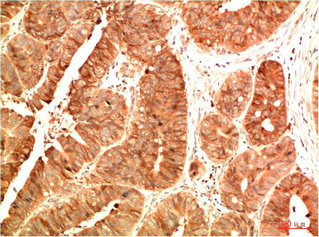

• Immunohistochemical analysis of paraffin-embedded Human Colon Carcinoma Tissue using Acetyl P53(K382) Mouse mAb diluted at 1:200.